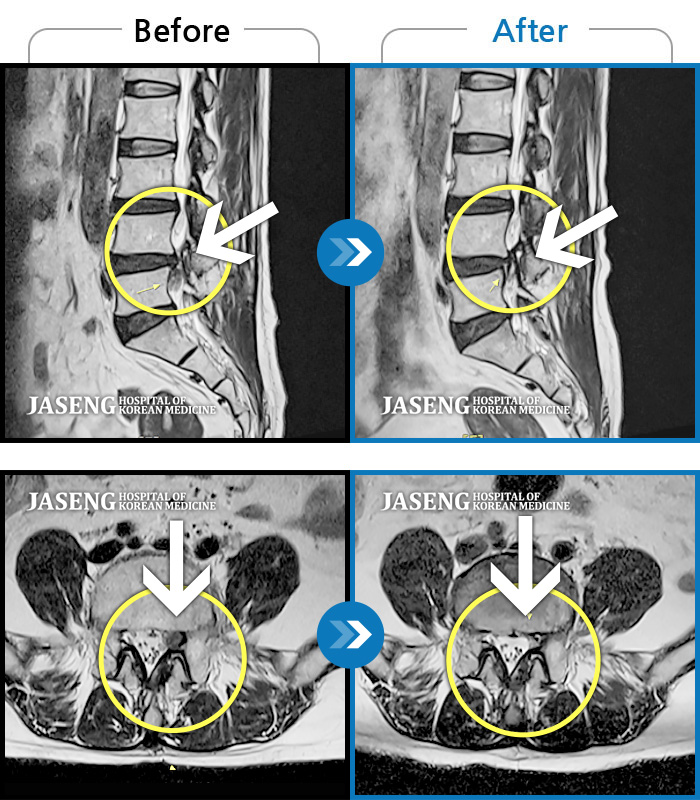

MRI 치료사례

허리 좌측 골반에서 발목으로 통증, 저린감, 쥐나는 증상